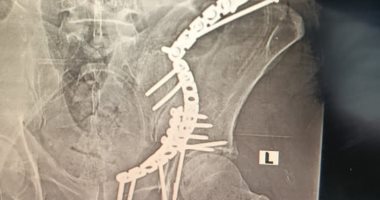

جراحة معقدة.. فريق بمستشفى النيل للتأمين الصحى ينقذ حياة شخص تعرض لحادث سير أشعة مقطعة تظهر الكسر

نجحت وحدة جراحات الحوض بقسم العظام مستشفى النيل للتأمين الصحي بشبرا الخيمة في محافظة القليوبية، بإجراء جراحة معقدة لمريض خمسيني كان يعاني من كسور متعددة بالحوض إثر تعرضه لحادث سير.

وكشفت المستشفي، في بيان لها، أنه تم تثبيت الكسور بشرائح متعددة من خلال مداخل جراحية مختلفة في آن واحد، وتم إعادة بناء الحوض بنجاح كبير والمريض في حالة التعافي والعلاج.